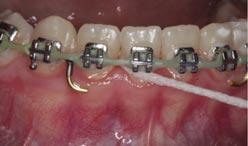

Research advocates for an improvement in gingival health when flossing is incorporated into oral hygiene routines (Figure 4).11 Zannata et al. found that there are small but statistically significant benefits to using dental floss in FA patients.1 In contrast to this, other studies have found insufficient evidence that routine instruction in floss use should be provided to all patients.12

Interdental brushes

IDBs are reported to be the most effective method of cleaning interproximal surfaces (Figures 5a, 5b and 5c). The evidence suggests superior plaque removal when compared to both toothbrushing alone and toothbrushing combined with floss.13 The added benefit is their ease of use in the presence of FAs, allowing for cleaning around

appliances, and therefore increasing compliance. IDBs as adjuncts to toothbrushing are recommended by several authors given their ability to more effectively remove plaque than brushing alone.14